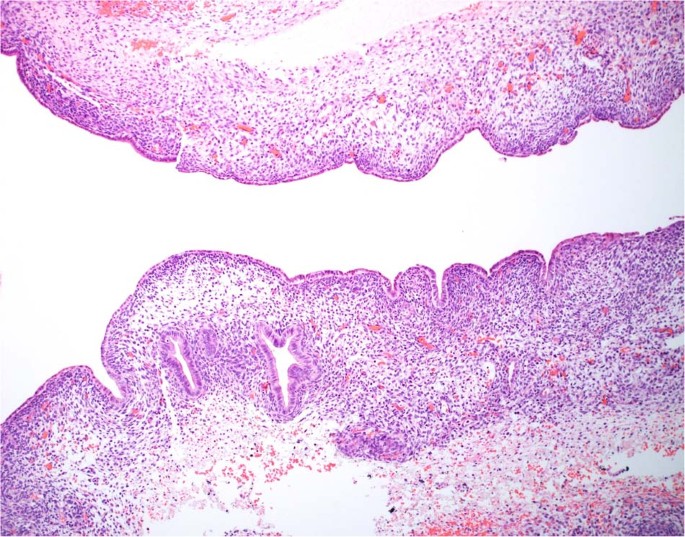

One of the early reports of cERMS consisted of 13 cases in patients between 12- and 26-years of age who presented with vaginal bleeding62. In contrast to vaginal RMS with a median age at diagnosis of 2 years, cERMS is seen in older children, adolescents and young adults with a median age of 13–14 years63. However, a vaginal biopsy of an ERMS does not permit a distinction between a vaginal and cervical origin, but as noted the age at presentation as well as additional clinical studies may be helpful in the individual case. Uterine RMS presenting in the cervix of an adult occurs in younger age women than in those arising in the corpus64. The cERMS typically has the features of the favorable botryoid ERMS with a cambium layer and in almost 50% of the cases foci of cartilage are identified, a seemingly unique feature of ERMS within the DICER1 setting unlike the absence of cartilage in the sporadic ERMS (Fig. 9A, B); this same combination of ERMS and cartilage is present in PPB as well as other DICER1-associated neoplasms. A noteworthy finding in the report of 13 cases was a prior history of SLCT in two patients; the authors stated that “the combination of a rare cervical tumor and a rare ovarian tumor in these two patients suggests more than a chance association”62. Subsequent reports have documented this association, one in a 27-year-old woman with a SLCT and a prior history of a cERMS at 14-years of age65, and another in a 13-year-old presenting with a synchronous SLCT and cERMS66.

A A polypoid “vaginal” tumor presented in a 9-year-old female showing scattered endocervical glands with variably prominent subepithelial concentration of small cells and nodules of cartilage. PPB-type IR was also detected in the lung and a pathogenic heterozygous germline DICER1 mutation was detected. B Endocervical gland encircled by embryonal rhabdomyosarcoma in an 11-year-old female with a cervical-vaginal mass. She subsequently developed a Sertoli-Leydig cell tumor at age 13 years and had a pathogenic heterozygous germline DICER1 mutation.